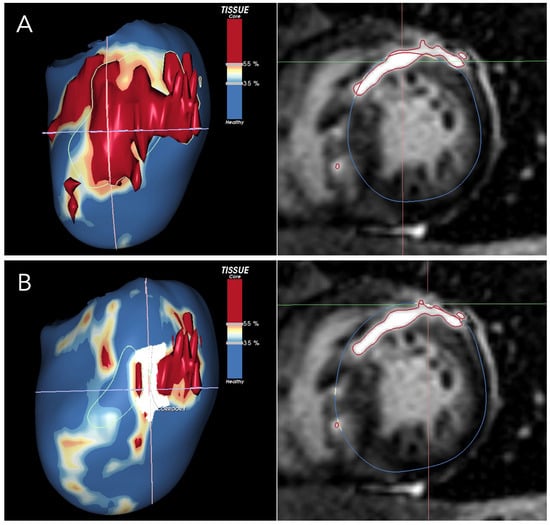

LGE in HCM patients reveals variations in presentation, signal intensity, and distribution independently of global scar extent []. This heterogeneity reflects the complex architecture of HCM scar tissue, which, unlike post-ischemic scars, consists of diffuse fibrosis combined with viable muscle fibers rather than dense subendocardial scarring confined to a specific vascular territory [,,,]. This complex architecture represents an ideal substrate for re-entry circuits. CMR studies showed that mild- or intermediate-enhanced LGE was more predictive of ventricular arrhythmias than hyper-enhanced LGE [,]. Furthermore, a recent study in low- and intermediate-risk patients demonstrated that a quantitative analysis of LGE dispersion is a predictor of major arrhythmic events independently of the total scar burden []. Visual scar heterogeneity evaluation can be challenging and is prone to significant interobserver variability. Radiomics has the potential to make this analysis more accurate and reproducible. A recent study conducted on a large unselected cohort of HCM patients demonstrated that scar heterogeneity assessed with LGE radiomics is a significant predictor of SCD risk and provides incremental risk stratification beyond the current risk models []. This suggests that a qualitative assessment of scar architecture through LGE signal heterogeneity may provide more detailed insights into the pro-arrhythmic substrate, enabling the risk reclassification of patients with mild-to-moderate LGE burden (<15%). The main limitation of assessing LGE heterogeneity with standard LGE images is its reliance on 2D imaging, which does not fully capture the complex three-dimensional architecture of scar tissue []. Recently developed post-processing software elaborated LGE images to obtain a more accurate evaluation of myocardial scar architecture [,]. By segmenting pixel signal intensity, these techniques enable differentiation between dense core fibrosis and diffuse border zone (BZ) fibrosis. They then reconstruct the data into 3D images and identify corridors of BZ tissue protected by dense scars or anatomical barriers that connect areas of normal myocardium between the core zones, referred to as border zone channels (BZCs) (Figure 1) []. From a functional point of view, BZCs are corridors of excitable myocardial tissue with slow conduction, electrically insulated by non-conductive scar tissue. By acting as slow-conducting re-entrant pathways, they can trigger and sustain ventricular tachycardia []. In this view, BZC may represent the imaging equivalent of the structural and functional substrate that promotes re-entrant VTs []. A recent CMR study demonstrated that BZCs are a strong independent predictor of ventricular arrhythmias in high-risk HCM patients and that risk assessment based on scar channels rather than total scar mass reclassified approximately 12% of patients, aiding in the identification of those at highest risk [].

Figure 1.

The figure shows a short-axis view of a CMR of a patient with HCM, highlighting an extensive scar involving the anterior wall and the interventricular septum. LGE-CMR images were post-processed using ADAS 3D (Galgo Medical, Barcelona, Spain), creating nine concentric surface layers spanning from the endocardium to the epicardium of the left ventricular wall thickness, resulting in a 3D shell for each layer. Color-coded pixel signal intensity (PSI) maps were projected onto each shell. Hyper-enhanced areas were classified as the core zone, borderline zone (BZ), or healthy tissue using thresholds of 40 ± 5% and 60 ± 5% of the maximum PSI. The scar-dense core is coded in red, BZ is coded in orange and white, and healthy myocardium is coded in blue. BZ channels are identified as continuous corridors of BZ protected by scar core tissue. In (A), the 50% layer is shown, representing the mid-myocardial layer. The area is entirely occupied by a dense and compact scar. In (B), the 3D reconstruction corresponds to the 80% epicardial layer. In the anterior wall, at the center of the crosshair, a BZ channel is visible.